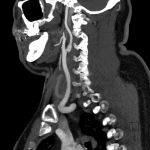

- Shelf-like smooth linear filling defect along the posterior wall of the right internal carotid artery just distal to the common carotid artery bifurcation

- Carotid webs characteristically arise along the posterior wall of the proximal cervical internal carotid artery and it is this location and their smooth, shelf-like contour that helps distinguish them from intraluminal thrombus or carotid dissection

- This characteristic appearance is often best appreciated on sagittal reformatted images